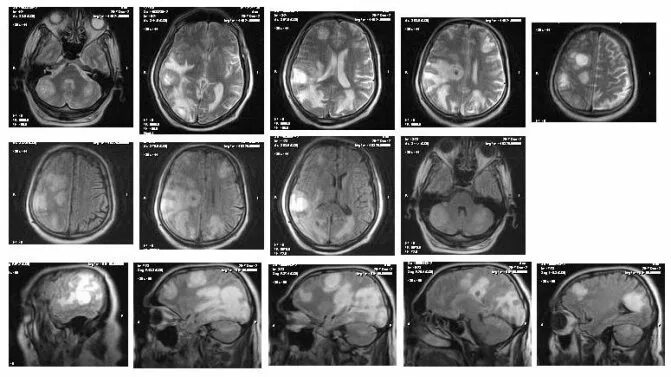

Метастазы головного мозга кт